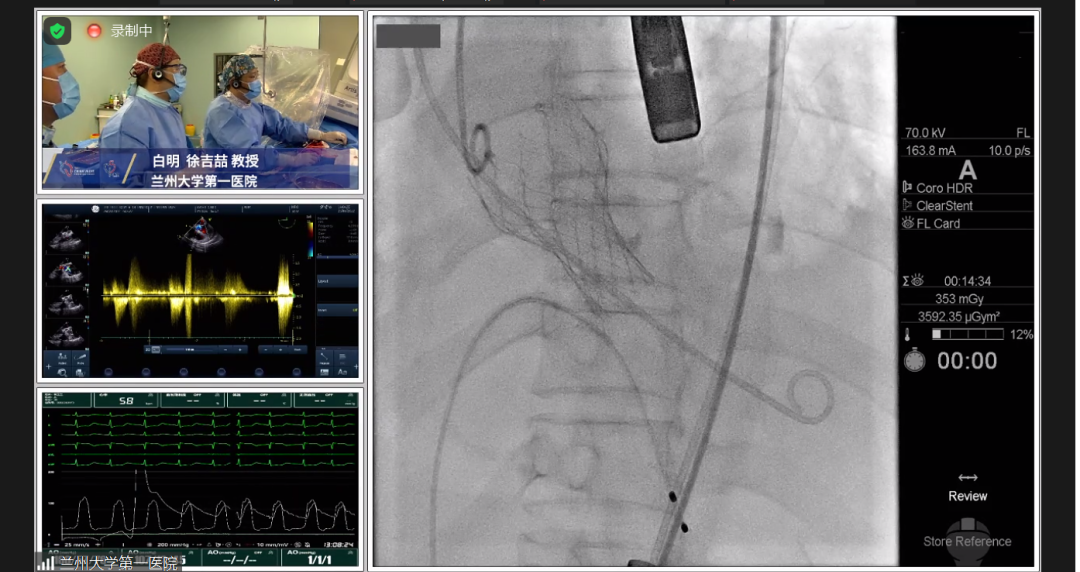

根据测得的瓣环直径,结合患者二叶式主动脉瓣,瓣叶见钙化,以及畸形的有效开口,术中决定采用Evolut PRO 23mm瓣膜。递送系统顺利过弓跨瓣,球囊预扩后目标深度开始释放,得益于可回收设计,术中再回收进行一次位置调整,最终目标位完美释放,瓣膜立即工作,展开形态良好,无冠脉阻挡,无传导阻滞发生,术后压差<10mmHg,血流动力学稳定,手术圆满成功。